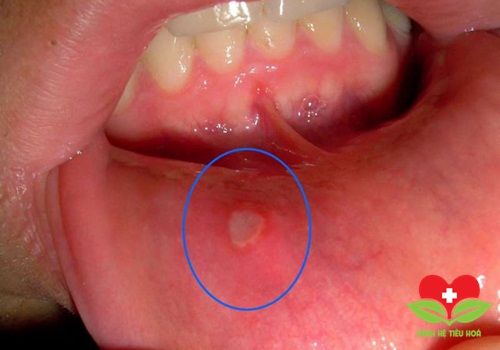

4. Bệnh lý viêm loét miệng: hay gọi là nhiệt khoang miệng, loét áp-tơ. Do nhiều nguyên nhân: nhiềm trùng, quá mẫn cảm, kích thích tố, stress, thiếu vitamin, sau sang chấn…thường trên lưỡi, má, lợi. Bệnh thường tự khỏi sau khoảng 2 tuần, nếu bệnh nặng có thể dùng thuốc, kem bôi giảm đau, hoặc dùng laser nha khoa.